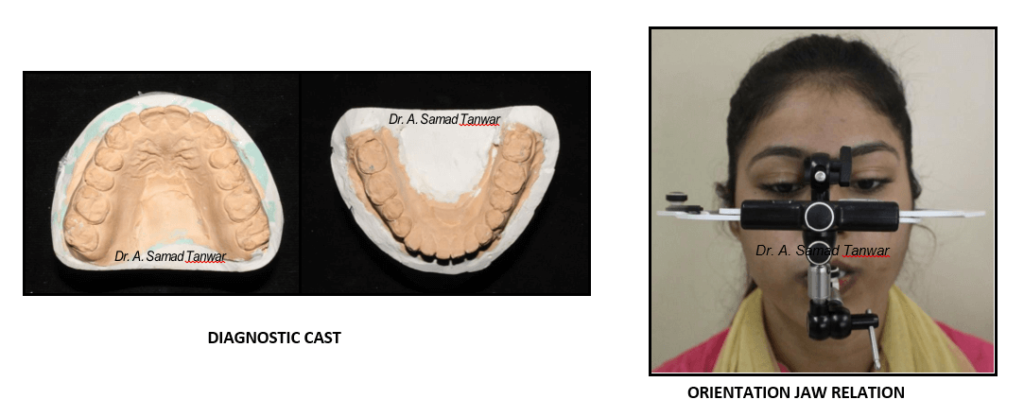

Diagnostic records were

The patient was guided into centric relation and it was mounted on a semi- adjustable

The articulator was programmed using protrusive and lateral interocclusal